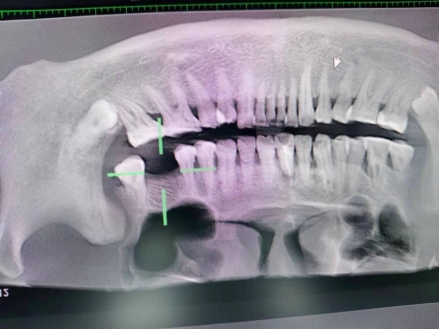

武先生术后检查图

据了解,53岁的武先生,因右上后牙缺失多年,缺失的牙齿给他造成了不小的烦恼,影响到了正常咀嚼功能。在了解到91直播 口腔科能开展种植牙手术以后,武先生前来咨询,经过仔细全面的口腔检查和CT检查、检验等检查,武先生符合种植牙条件,决定实施右上后牙区种植牙的修复方案。本次手术由陈河林博士主刀,黄魁副主任做助手,在口腔中心成功完成该院首例种植牙手术,手术历时约30分钟,术中微创操作,患者全程无痛,术后无不良反应,整个诊疗过程舒适、安全、精准,经术后CT检查种植体位置精确。